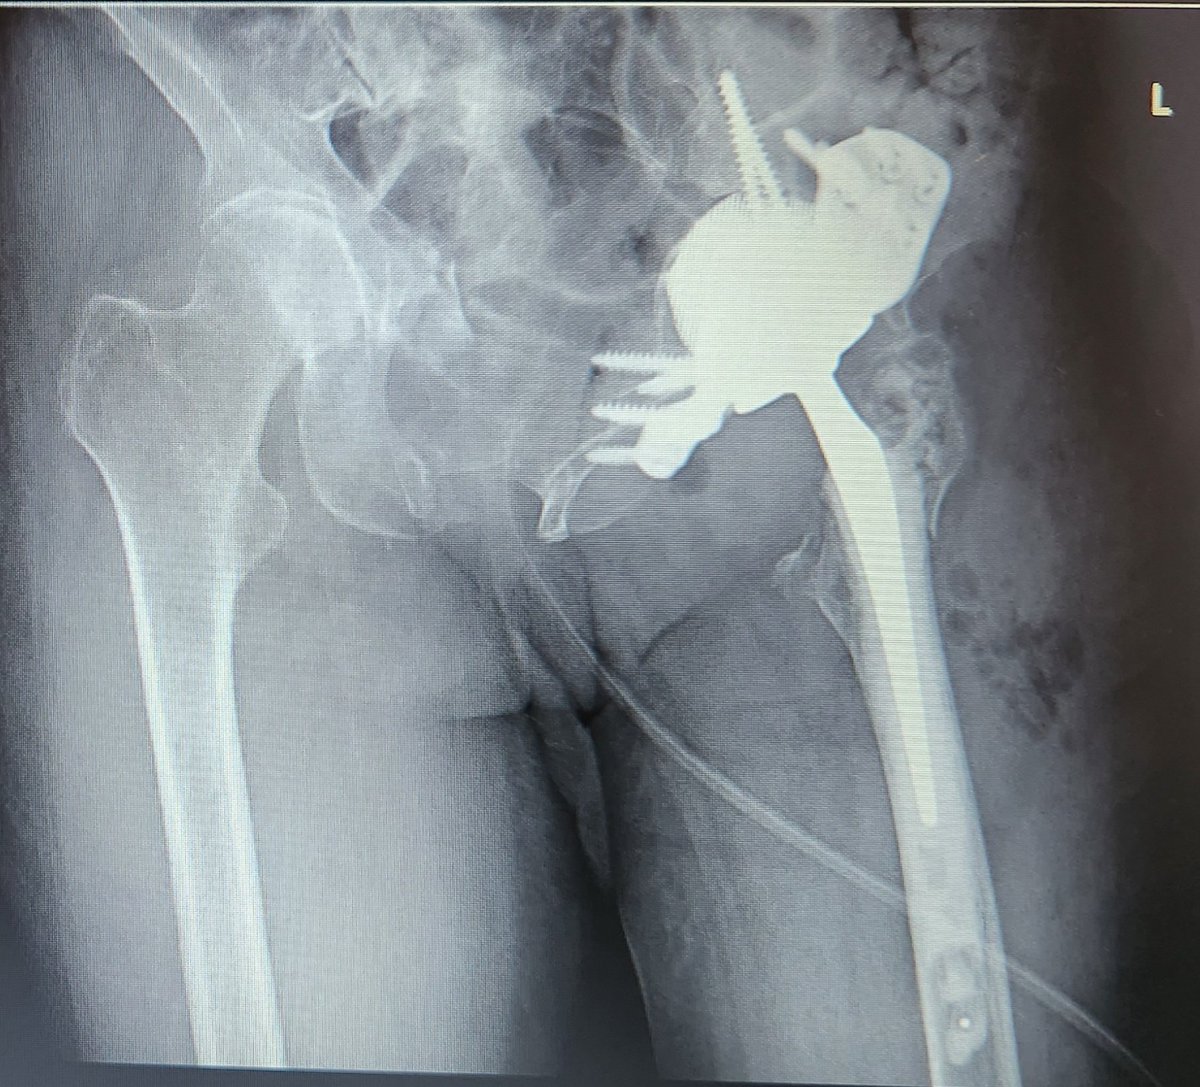

These are expensive too and a lot of hard work goes into getting pt on table. Thank you to YGC theatres & staff for the effort, @BetsiCadwaladr for support, fantastic MDT Wrightington, North Wales MDT, surgical experience @CavendishHip, my colleagues & Mr Kapur for dual operating